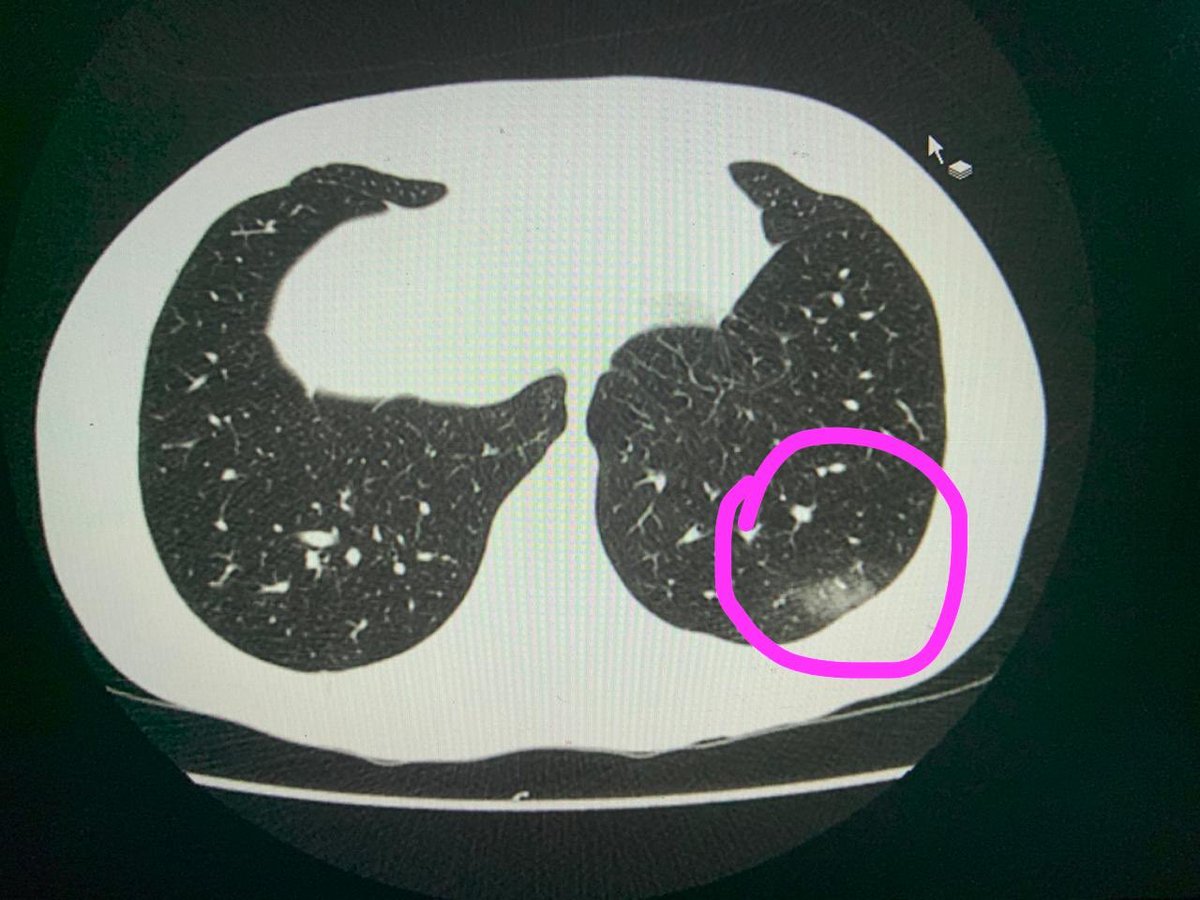

Muita gente chegando no hospital com AVC ou oclusão arterial aguda após quadro de covid.

O exame que pode prever isso é chamdo D-DIMERO.

Meu D-DIMERO deu aumentado.

Daí além do coquetel pra COVID, com antibiótico e medicações sintomáticas, tive que tomar anticoagulante pra evitar eventos pró-trombóticos.